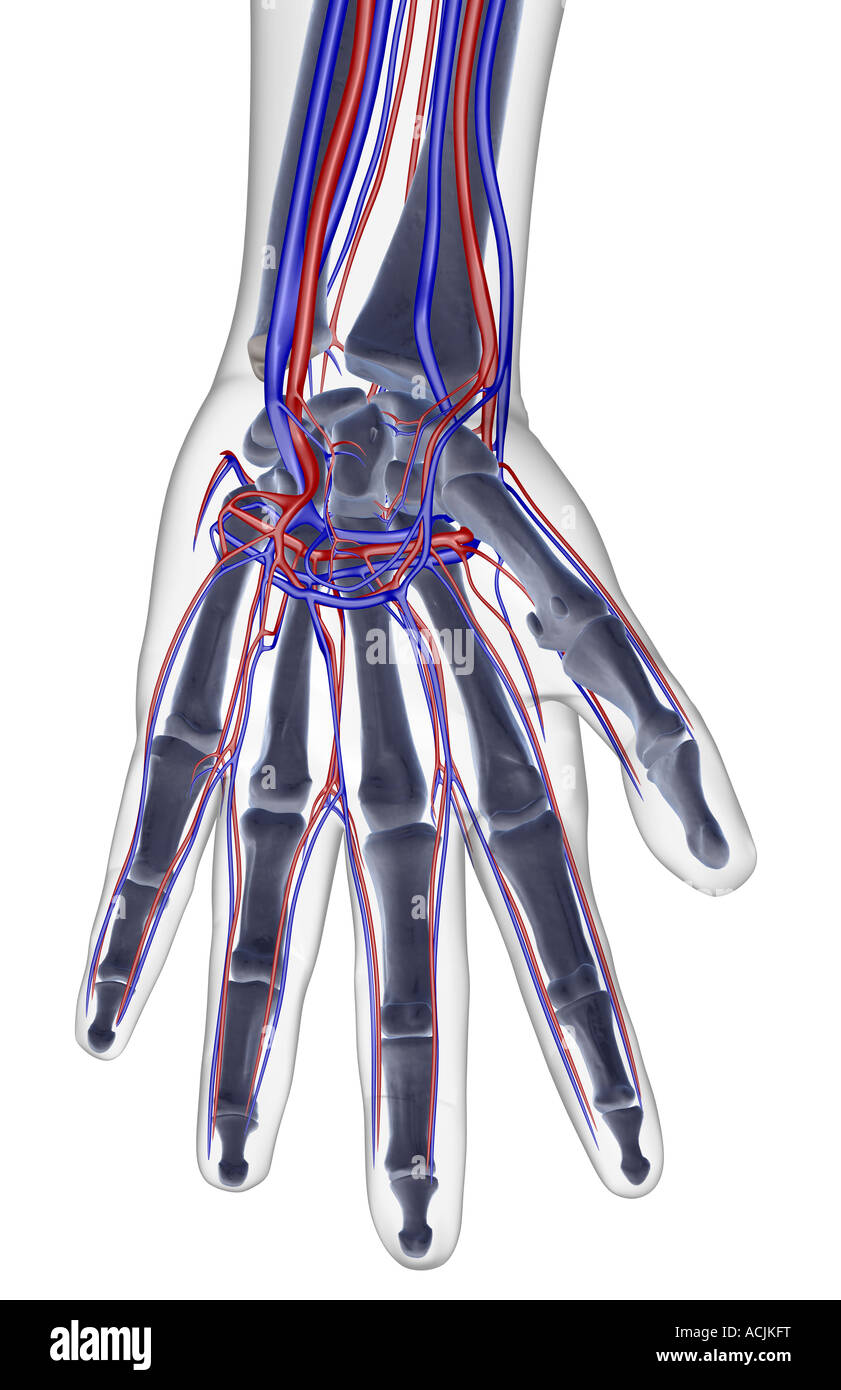

The blood supply of the hand Stock Photohttps://www.alamy.com/image-license-details/?v=1https://www.alamy.com/stock-photo-the-blood-supply-of-the-hand-13170620.html

The blood supply of the hand Stock Photohttps://www.alamy.com/image-license-details/?v=1https://www.alamy.com/stock-photo-the-blood-supply-of-the-hand-13170620.htmlRFACJGXN–The blood supply of the hand